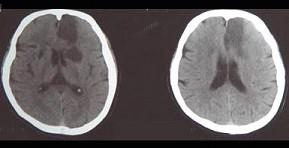

问题 患者,78岁,有高血压病史8年,突发一侧下肢无力,伴少语2天入院,行头颅CT出现如图所示脑梗死,该病灶最可能是下列哪条阻塞引起 ( )

选项 A、脉络膜前动脉 B、豆纹动脉 C、颈内动脉主干 D、大脑中动脉主干 E、大脑前动脉主干 单选题

答案 E